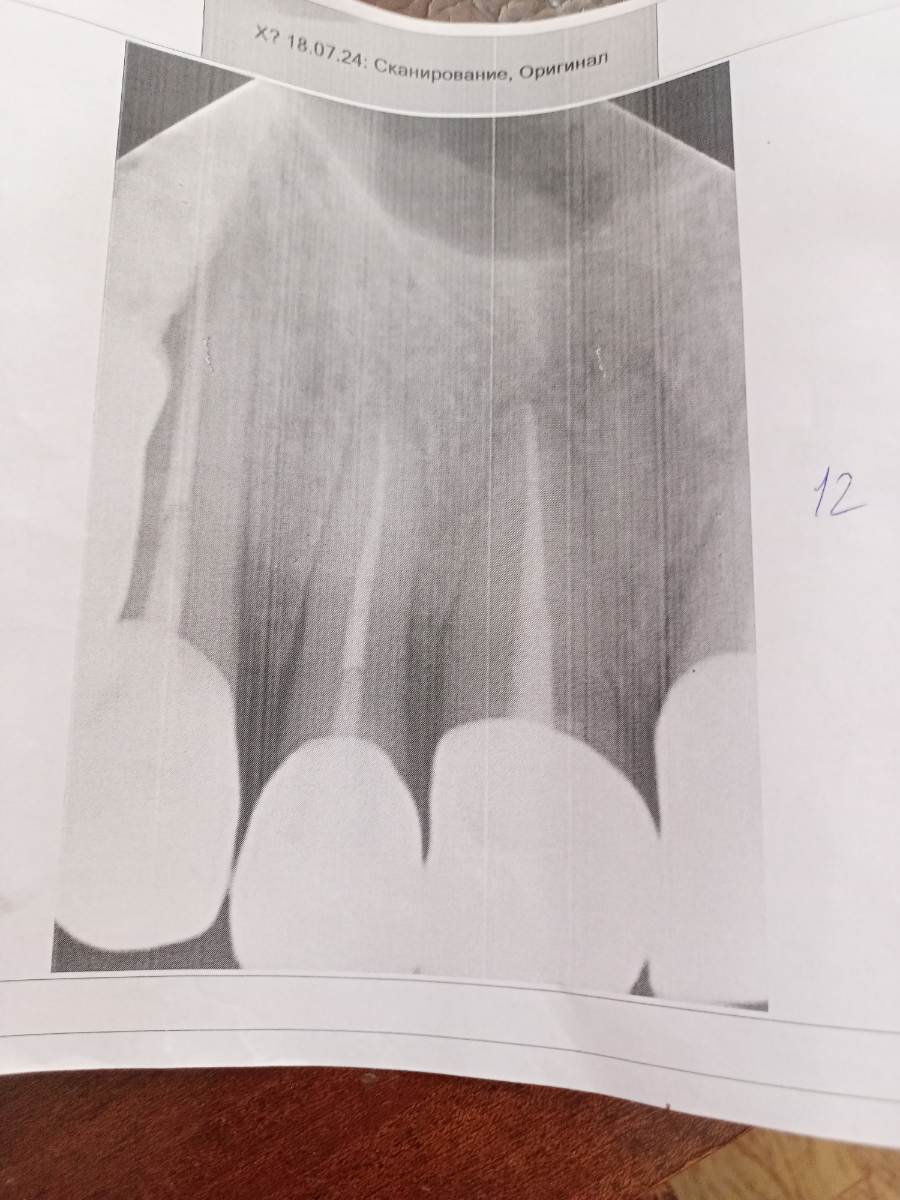

VelikoMu4ennik Опубликовано 20 июля, 2024 Поделиться Опубликовано 20 июля, 2024 (изменено) Было протезирование с перелечиванием каналов года два назад. После переохлаждения в районе 2-ки сверху появилась шишка на десне, а ещё через неделю - две образовался как я понял свищ в этой шишке. Сходил к хирургу, он сказал что свищ есть и направил на рентген. Сделав Рентген, спросил у рентгенолога - есть ли воспоминание у корня 2-ки? Ответ - на 2-ке нет, но есть немного на 1-ке(что то там добавил про может я яблоко поел). Показал хирургу и он сказал по снимку что то невнятное. Подскажите пожалуйста, воспаление у верхушки 1-ки, а на 2 -ке нет? И есть ли киста? (На фото я вижу справа (от верхушки корня 1-ки, на котором коронка бОльших размеров ) идёт как бы такой шарик вправо, но не спец по снимкам) А также можно ли сделать резекцию корня в этом случае чтобы не спиливать коронку? Изменено 20 июля, 2024 пользователем VelikoMu4ennik Ссылка на комментарий

VelikoMu4ennik Опубликовано 20 июля, 2024 Автор Поделиться Опубликовано 20 июля, 2024 Спасибо за участие. А вот эта вот затемненная область, не является ли кистой? Ссылка на комментарий

Doc Опубликовано 20 июля, 2024 Поделиться Опубликовано 20 июля, 2024 Плоские снимки сами по себе бывают малоинформативны, лучше 3D. Распечатанные на бумаге они становятся еще менее информативны. Сфотографированные с бумаги и пересланные в интернет при помощи разных программ сжатия — вообще никакие. 3 Ссылка на комментарий